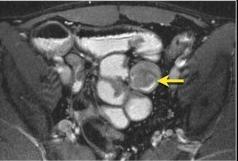

Polyp adenomateux : ( Image IRM T2 fat

sat ) Masse arrondie a iso-signal de l'intestin (

fleche jaune ) a limite net et a bord lisse . |